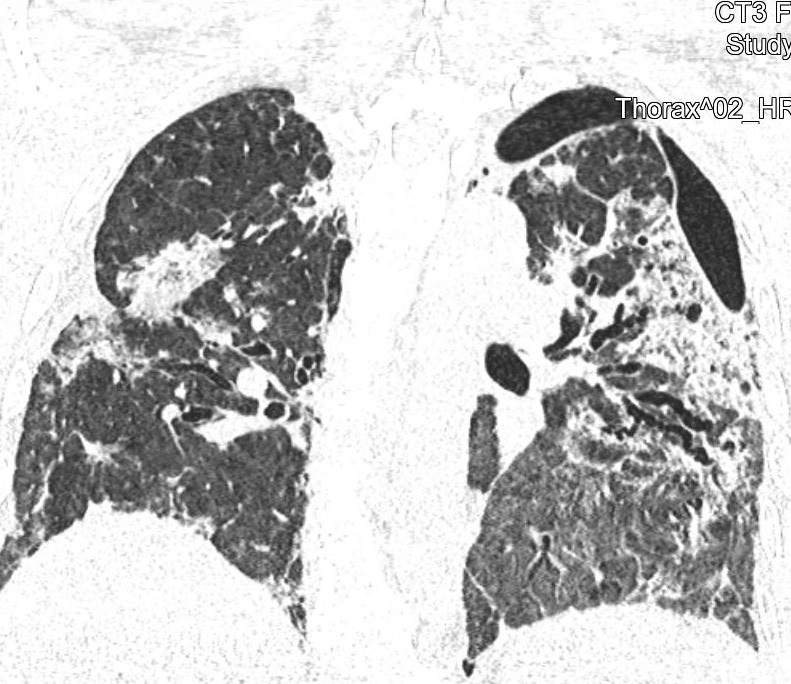

CT snímky vývoje patologických změn na plicích po prodělané nemoci covid-19 u třiapadesátileté doposud zcela zdravé pacientky (fotografie CT nálezu publikovány se svolením Dr. Evy Kočové, Ph.D. – RDG klinika):

Obr. 4: V říjnu 2021 bylo provedeno poslední CT vyšetření (osm měsíců od vzniku onemocnění), konečně dochází k hojení a mizení patologických změn. Pacientka intenzivně rehabilituje, už nepotřebuje domácí kyslíkovou léčbu.